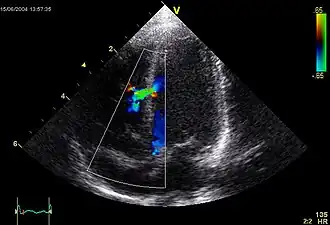

![]() Эхокардиографическое изображение дефекта межелудочковой перегородки в мышечной части. | |

При доплер-ЭхоКГ уточняется место расположения дефекта, его размер, определяется давление в правом желудочке и лёгочной артерии. В первой стадии лёгочной гипертензии давление в ПЖ не превышает 30 мм.рт.ст., во второй стадии — от 30 до 70 мм.рт.ст., в третьей — более 70 мм.рт.ст.[6]